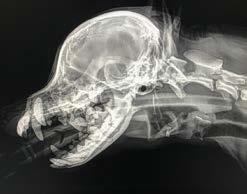

v-gel® advanced DOG

Supraglottic Airway Device

Each dog v-gel® unit comes with a free gastric tube.

• Gastric channel – With insertion of oesophageal or gastric tube, allows for greater protection and management of reflux/regurgitation and aspiration.

• Single use – Human medicine standards of hygiene.

• Anatomical matching features combined with a soft material to give a high quality pressure seal.

• Perfectly suited to ventilated as well as spontaneously breathing patients.

• Avoids laryngeal and tracheal trauma, which means safer anaesthetics and superb comfortable patient recoveries.

• Fast, easy, safe and stress-free insertions.

• No post-operating coughing or gagging.

• Low airway breathing resistance due to the large airway channel within the device.

• High quality pressure seal restricting leakage of volatile anaesthetic agents, thus improving health and safety for staff.

• Suitable for a variety of patients including brachycephalics, and procedures including dentals.

v-gel® advanced devices are suitable for a wide variety of procedures, including dental procedures.